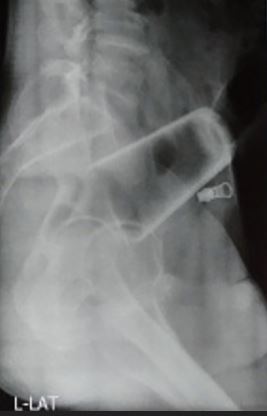

After an X-ray was done, doctors tried to remove it but couldn’t get a grasp on the glass as it was inverted.

Medical staff then performed an exploratory laparotomy, which is a surgery to open up the abdomen.

At that point, they attempted to move the glass out by “milking” or squeezing the lower intestine.

“Milking was attempted to deliver the glass through the an*s, but this was unsuccessful as the glass was high up, inverted and tightly wedged,”

the journal explained.

“Hence sigmoid enterostomy was done and the glass was extracted.”

An enterostomy is the surgical incision into an intestine, allowing doctors direct access to the glass